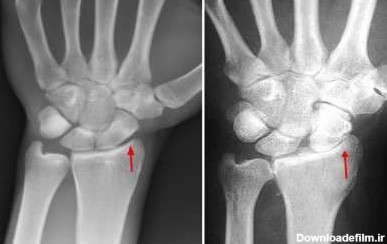

عکس مچ دست برای تعیین سن استخوانی

تشخیص سن استخوانی کودک با رادیولوژی یا رادیوگرافی یکی از گام های مهم در بررسی بیماری ها و نارسایی های ژنتیکی به حساب می آید.

تشخیص سن استخوانی با رادیولوژی در تهران کجا انجام دهیم؟ آیا تشخیص سن استخوانی با رادیولوژی عوارض دارد؟ روش انجام تشخیص سن استخوانی با راد